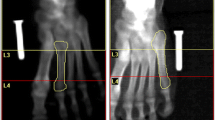

The disarticulated right hind limb was assessed with all soft tissues intact. The scan length was determined by the length of the bone (the scan area was approximately 50 mm × 130 mm). Each leg was placed in a supine position on the scan table, and a cranio-caudal (anterior-posterior) scan was performed. The leg was then medially rotated and a lateral scan was performed. Bone mineral density (BMD), bone mineral content (BMC) and bone area (BA) values were obtained with the “manual analysis” facility. The height of the boxes was determined by the height of the regenerate, and all box widths were identical (15 mm). Using the software “ruler”, the distance from the knee to the top of the regenerate and the height of the regenerate were measured and recorded. A “region of interest” (ROI) box was placed over the regenerate. The height of the ROI was such that the entire length of the regenerate was included. The boxes were positioned so that all the bone and some soft tissue were included in the region of interest (Fig. 1).

The software calculated BMC (g), BMD (g/cm2), average bone width (cm) and average bone area (cm2). vBMD was calculated manually assuming that the bone was an elliptical cylinder.

The volume of the region V = Cross-sectional Bone Area × ROI HeightThis assumes that the regenerate bone is homogenous throughout the ROI. The plain radiographs suggest that this is a reasonable assumption.